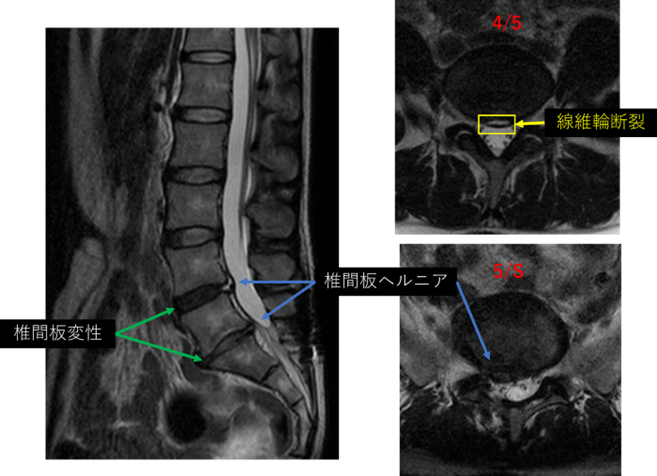

画像及び所見について

L1/2: 異常なし

L2/3: 異常なし

L3/4: 異常なし

L4/5: 変性、ヘルニア、繊維輪断裂

L5/S: 変性、右ヘルニア

以上の事が画像上認められます。

4/5、5/S に椎間板変性、椎間板ヘルニア、繊維輪断裂 を認め、主症状の原因の可能性が高い。